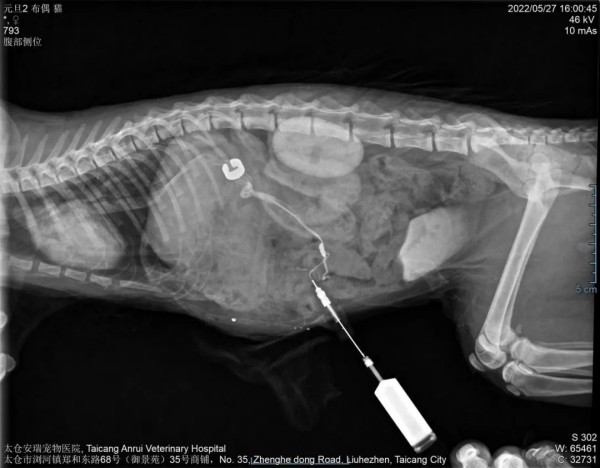

患猫品种为布偶猫,雌性未绝育,4月龄,2.38kg,免疫驱虫全。主诉在家吃完罐头后,突发流口水,咀嚼痉挛,5分钟后自行恢复正常,然后带去周边医院检查,经过血检,X光等检查该医院初步诊断口炎和肺部炎症经过治疗几天后未好转,吃完食物后再次发病且频繁发病时间也有所延长,发病后精神沉郁。后带到金医生的医院进行检查。刚到医院时,猫咪的精神状态良好,未见流涎,体温38.6℃,心率为135次/min,呼吸(P)和毛细血管再充盈时间(CRT)均正常。猫咪消瘦,体况评分为3/9,触诊腹部柔软。双眼虹膜颜色异常改变,呈深棕色(铜色),检查过程中突发咀嚼痉挛,共济失调,流口水,中枢性失明,癫痫后晕厥呈现半休克状态,医院团队立刻对猫咪进行了抢救,抢救2小时后恢复饮食,在抢救过程中同时进行实验室和影像学检查。通过NH3血氨检查测定动物血清中血氨的含量,升高提升肾脏或肝脏的疾病。提示有肝性脑病,门脉分流可能。超声检查结果显示:可见异常增粗异常走向的血管,高度怀疑先天性门体分流,肝外胃-十二指肠静脉分流。与主人沟通后选择使用Ameroid渐缩环进行门脉分流阻断。随后金医生对猫咪进行了手术,手术进行的非常成功。术后猫咪坚持食用肝脏处方粮(肝细胞需要再生和适应新循环的时间)+罐头(增加营养),体重慢慢增长上去了,根据血检指标情况抗生素和乳果糖等药物逐渐减少至停药。后期B超复查显示血管环结扎已完全闭合,猫咪逐渐恢复了往日的活力。